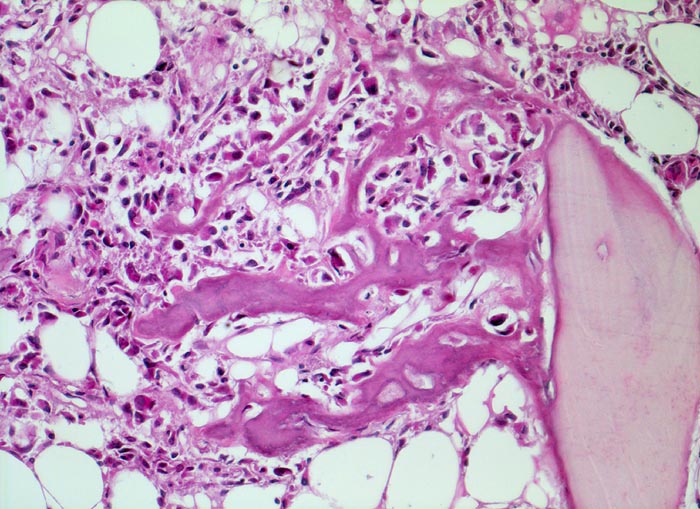

PathoPic – image database / PathoPic ID 4792 - Osteosarkom

Osteosarkom

maligner Tumor

Knochen, Femur

Erhaltenes Spongiosabälkchen aus Lamellenknochen. Die Tumorzellen benutzen das ortsständige Knochengewebe als Leitschiene zum Anbau von Tumorosteoid.

16 jähriger Jugendlicher mit seit mehreren Wochen bestehenden belastungsunabhängigen Schmerzen im distalen Femur rechts oberhalb des Knies (Metaphyse). Im Röntgenbild irreguläre Verdichtung, zum Teil auch Aufhellung der ursprünglichen Knochenstruktur mit Zerstörung der Corticalis und spiculaartige (=sonnenstrahlenähnliche) Periostreaktion. Im Serum erhöhte alkalische Phosphatase.

Histologie

200